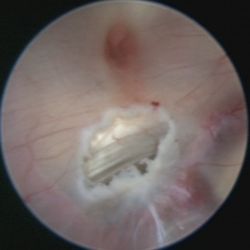

In diesen Fällen besteht die Behandlung mitunter in der Anlage eines alternativen Abflussweges aus dem Hirnwasserkammersystem in die das Gehirn umgebenden Zisternen (=Ventrikulozisternostomie). Dies geschieht durch einen minimalinvasiven, endoskopischen Eingriff. Ein Endoskop ist eine Art medizinisches Teleskop, das man über ein Bohrloch in die Hirnwasserkammern einführt. Da diese mit klarem Nervenwasser gefüllt sind, bietet sich eine gute Sicht auf die Wände und Strukturen der Kammern. Von oben kommt man durch eine Öffnung (Foramen Monroe) vom Seitenventrikel in den dritten Ventrikel. Mit feinen Instrumenten – wir verwenden routinemäßig einen Laser – wird der dünne Boden des dritten Ventrikels eröffnet

Präoperative MRT Untersuchung. Der rote Kreis zeigt den Boden des 3. Ventrikels, welcher im Rahmen einer endoskopischen VZS eröffnet wird.